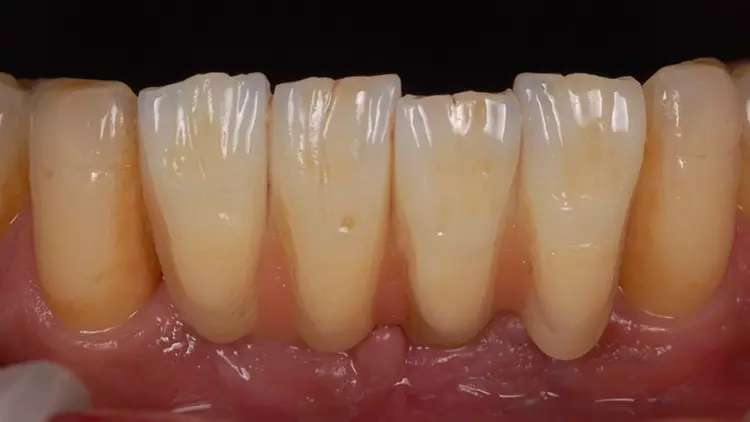

Als Interimsversorgung wurden herausnehmbare, klammerverankerte Prothesen aus Methylmethacrylat verwendet. Nach der dreimonatigen Einheilzeit erfolgten die Implantatfreilegung und die Versorgung mit Einheilkäppchen. Bei der Freilegung der Implantate und der Versorgung mit Einheilkäppchen sowie zum Zeitpunkt der Abformung mit den Abutments in situ lag eine reizlose klinische Situation ohne Anzeichen einer Entzündung im Implantatbereich vor (Abb. 4 und 5).

Der fehlende Zahn 24 wurde ebenfalls mittels eines Semados RS Implantats (BEGO Implant Systems GmbH & Co. KG) mit einer Länge/einem Durchmesser von 4,1/10,0 mm und einer monolithischen Zirkonoxidkrone ersetzt (3D Pro). Die klinische Situation konnte im Rahmen einer Nachuntersuchung im September 2022, fast zweieinhalb Jahre nach der Versorgung im Mai 2020 als sehr gut bezeichnet werden (Abb. 17-20).